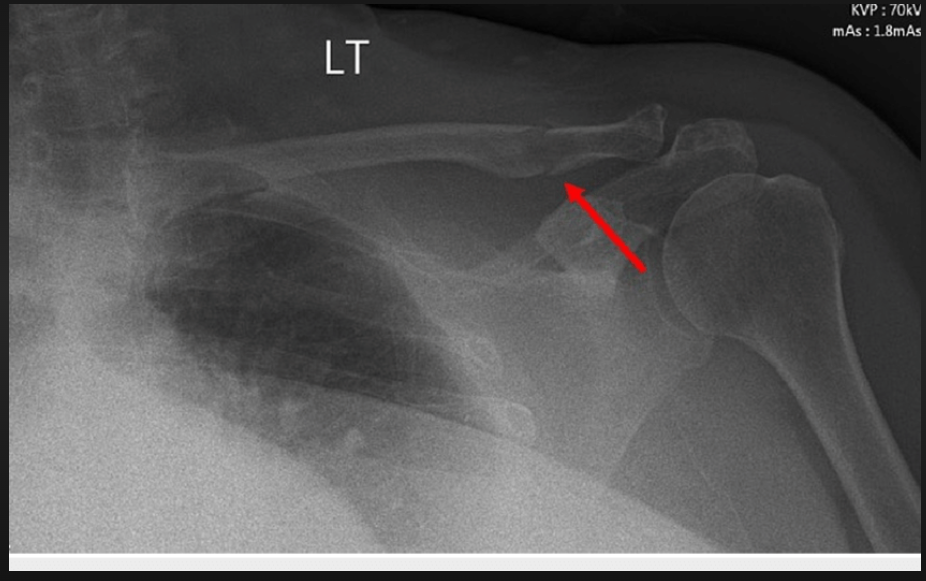

| Yesterday | Fractured left patella, left clavicle. C spine clear. Head CT – no signs of brain injury | Fractured Patella X-Ray Fractured Left Clavicle C-Spine X-Ray | ||||||||